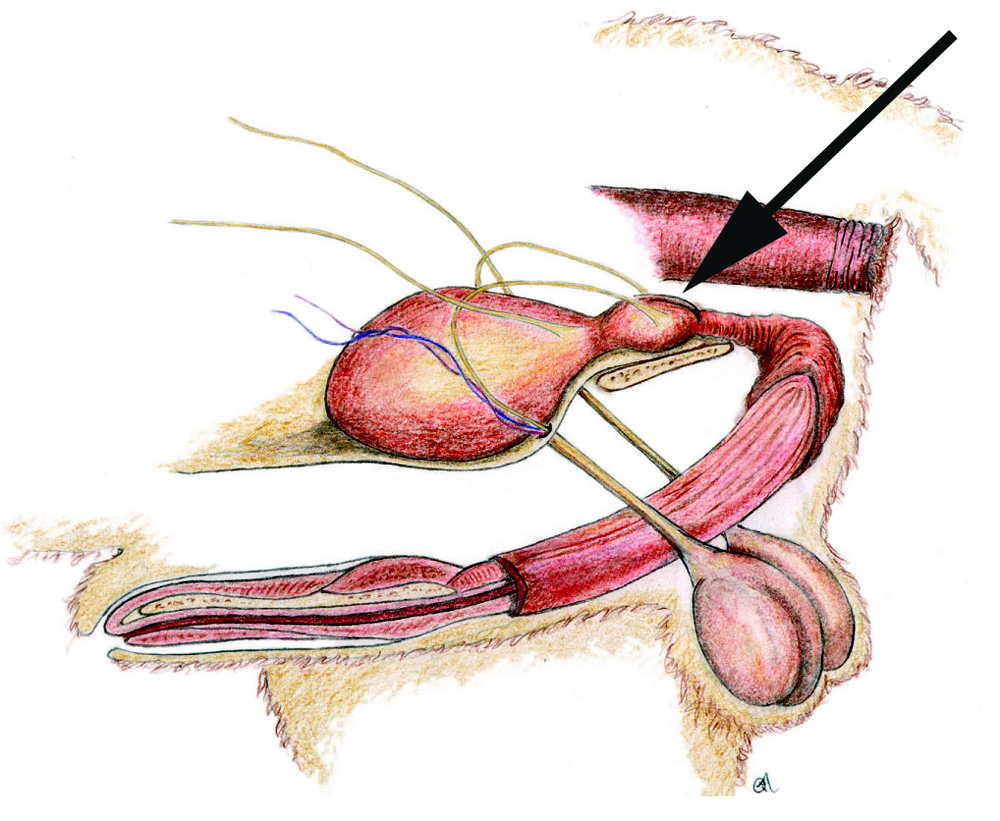

De prostaat is een geslachtsorgaan dat in de bekkenholte van het mannelijke dier ligt. De plasbuis en zaadleider komen in de prostaat samen. De prostaat produceert vocht dat tijdens de ejaculatie met het sperma vermengd wordt en dient als transportmedium voor het sperma.

In een heel enkel geval is er sprake van kanker in de prostaat. Deze aandoening is vrijwel altijd kwaadaardig en kan erg slecht worden behandeld. Doordat het gezwel op de plasbuis kan gaan drukken kan uw hond bijvoorbeeld steeds moeilijker plassen of poepen. De diagnose wordt gesteld doordat er onder echobegeleiding een monster van de prostaat wordt afgenomen en opgestuurd voor beoordeling door een patholoog.